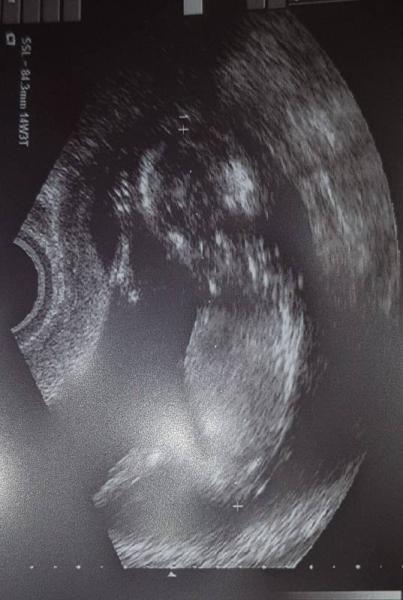

Huhu ihr Lieben! Ich war heute Außerplanmäßig beim FA, weil ich den Verdacht auf einen Pilz hatte. Hat sich bestätigt, aber ich hatte dann immerhin gleich meine Vorsorgeuntersuchung, die ich eigentlich erst nächste Woche gehabt hätte. Aber leider kein Outing. Dafür ist mein Krümel auf dem US 5 Tage weiter, als er laut ET wäre

Bild zu Außerplanmäßiger FA-Besuch - Forum für Januar - Mamis

Laut Ultraschallbild würde ich sagen SSL 84 mm

Genau, 8,43cm